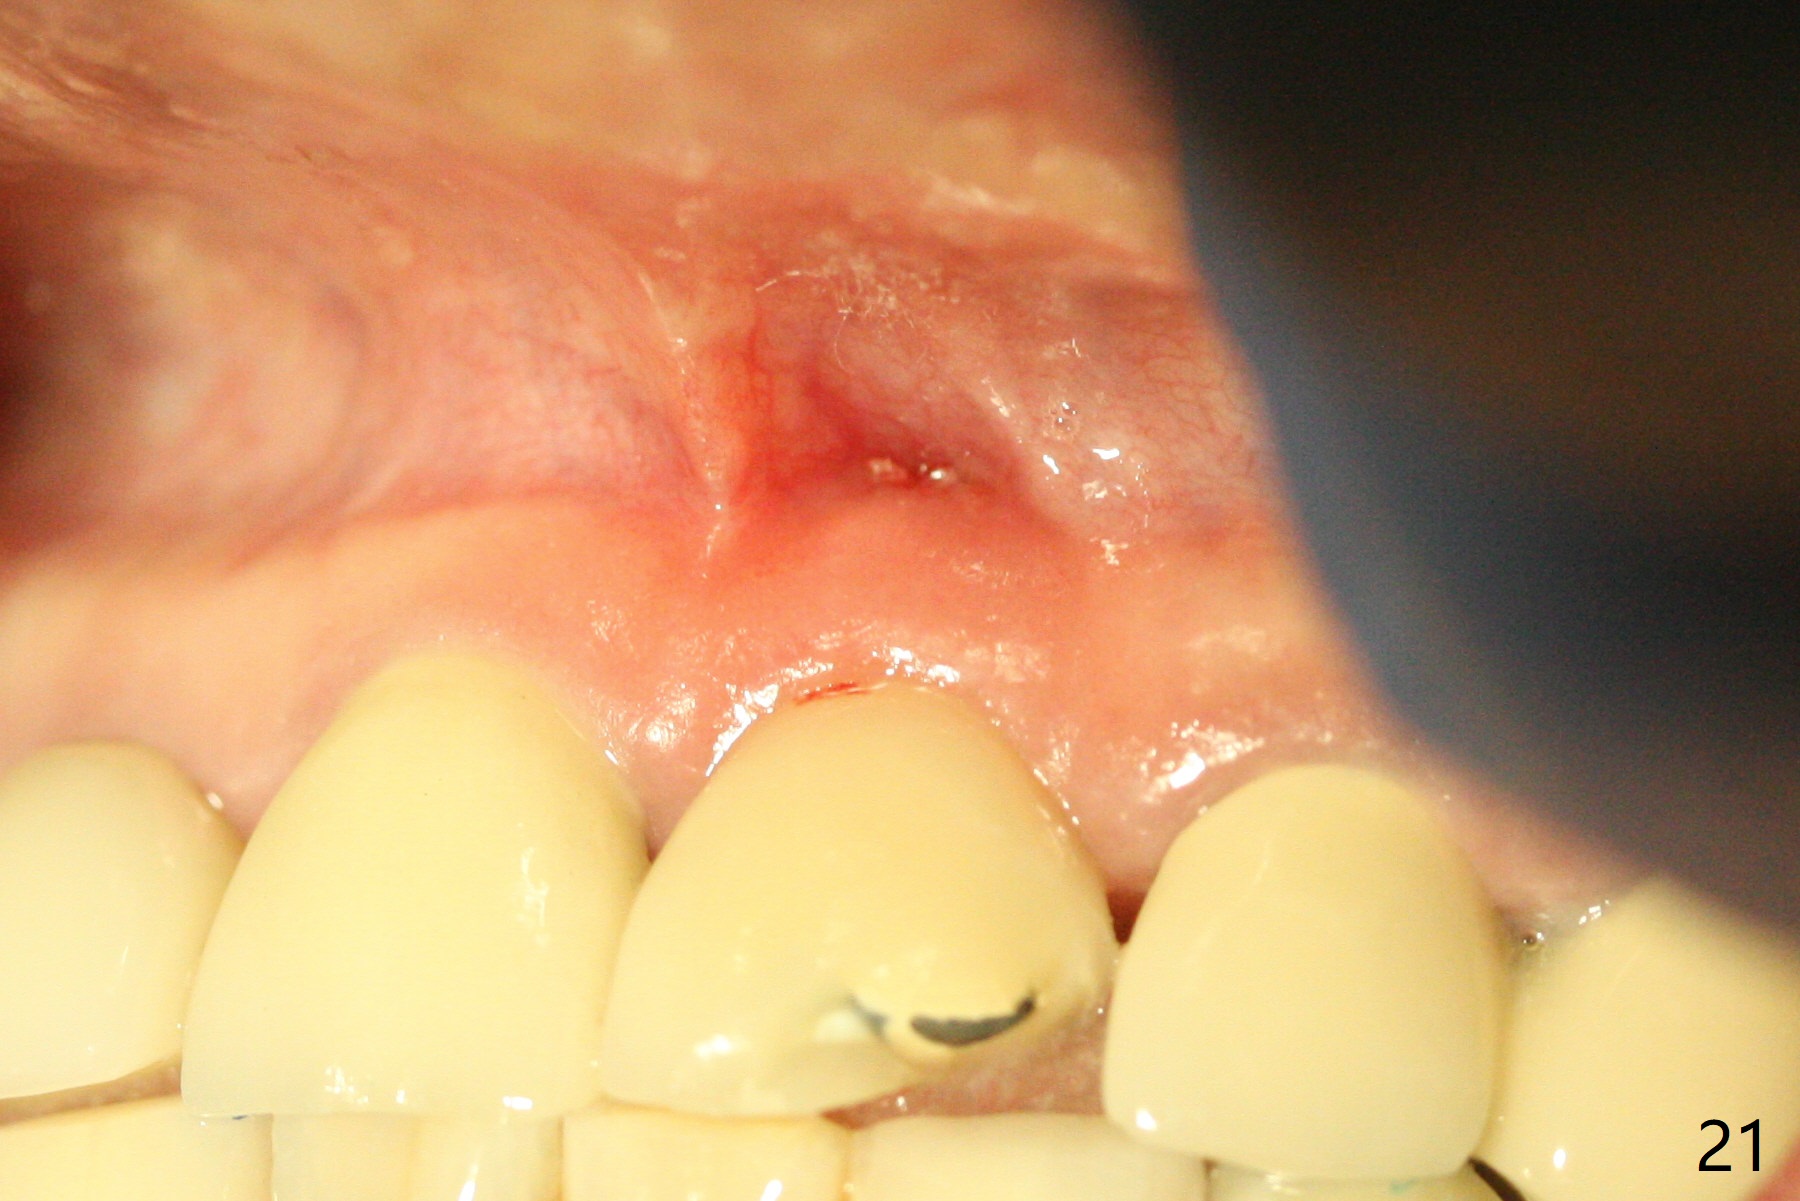

Nasal Floor

The buccal contour at #9 seems to be slightly concave preop (Fig.1,2 (*)). In fact the buccal plate is found to be lost when the tooth is extracted. Osteotomy is initiated as palatal as possible apical, but the occlusion dictates the coronal end of the osteotomy should be buccal, leaving the buccal gap ~ 2 mm for bone graft. The initial osteotomy (18 mm deep) appears to be close to the Incisive Foramen (Fig.3 blue dashed line). The nasal floor appears to be intact when the drill is removed. Subsequent osteotomy is adjusted so that the apical end of the osteotomy moves distal; when a 3.8x15 mm dummy implant is partially placed, there is clearance (Fig.4). It remains so when a definitive implant is seated (Fig.5); Vanilla graft is placed (Fig.5 *) before placement of a 4.5x5.5(3) mm abutment. More allograft is placed when an immediate provisional is fabricated (Fig.6 arrow and *). The gingiva remains to be recessive 1 month postop (Fig.7). It seems to be related to the bulky gingival margin of the provisional (Fig.8 *). After trimming the latter (Fig.9 *), the gingival margin immediately returns close to normal (Fig.10). The gingival margin is even between #8 and 9 two months postop, but the bone graft is exposed apically (Fig.11 ^). It may heals by itself. Otherwise debridement, regraft, PRF and suture are pending. The coronal portion of the socket heals 4 months postop (Fig.12). The gingival cuff forms by the immediate provisional (which is removed for impression) 4 months postop (Fig.13 *). While the full Zirconia crown at #7 remains intact (Fig.14), the PFM at #9 has porcelain chip (Fig.15). It is partially due to the occlusion; while the crown at #7 has clearance with the opposing dentition (Fig.16 *), the one at #9 has no. The access hole at #9 (Fig.17 *) seems to weaken the crown structure. There is no access hole at #7. No solid posterior support is another contributing factor for chip (Fig.18). The buccal plate has mild atrophy at #7 and 9 (Fig.19 *). A piece of bone graft is being expelled apically at #9 (Fig.20 >) and is removed subsequently (Fig.21). Before impression for repacking porcelain, the opposing incisal edge has been shortened (Fig.22 arrows, as compared to Fig.16). Since the ideal access hole is at the incisal edge (Fig.25 black circle), buccal to the existing one (Fig.24 A), the abutment is torqued before the repaired crown is recemented (Fig.23). Finally the crown has occlusal clearance (Fig.26). Porcelain chips again around the access hole of PFM 1.5 years post 2nd cementation. The dense bone at the crest (*) cannot explain why the abutment is not loose, since it remains incompletely seated (>). As it was trimmed short, an angled abutment is used (Fig.28). The coronal end is lingual, while #9/24 is edge to edge. The lingual aspect of the coronal end of the abutment is heavily trimmed to reduce bulkiness. To prevent chip, Zirconium crown will be fabricated in spite of the fact that it does not match the PFM of #8 (potential shade discrepancy). The patient is pleased with the new Zirconia crown (Fig.29).